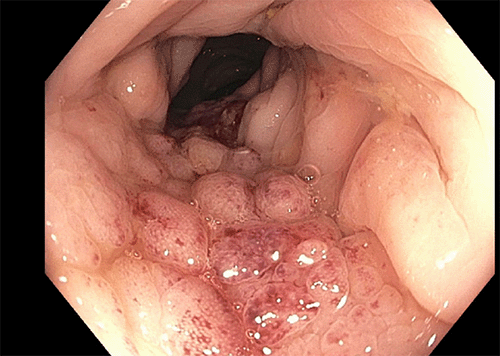

A 72-year-old Hispanic male with chronic kidney disease and type II diabetes was seen at the colon and rectal surgery clinic at John H. Stroger Hospital of Cook County for a suspicious colonic mass near the hepatic flexure. The patient initially complained of left flank pain and weight loss. A computerized tomography (CT) scan of the chest, abdomen, and pelvis showed a 3.5 × 3.5 cm lesion at the hepatic flexure associated with fat stranding, likely representative of direct local infiltration, multiple mesenteric lymph nodes and no sign of distant metastasis (Figure 1). Carcinoembryonic antigen level (CEA) was 1.34 ng/mL. He underwent a diagnostic colonoscopy with a biopsy of the lesion, revealing findings consistent with an inflammatory process (Figure 2).

Figure 1. First Abdominal CT Scan Showing Hepatic Flexure Lesion. Published with Permission

Figure 2. First Colonoscopy Showing Intraluminal Mass. Published with Permission